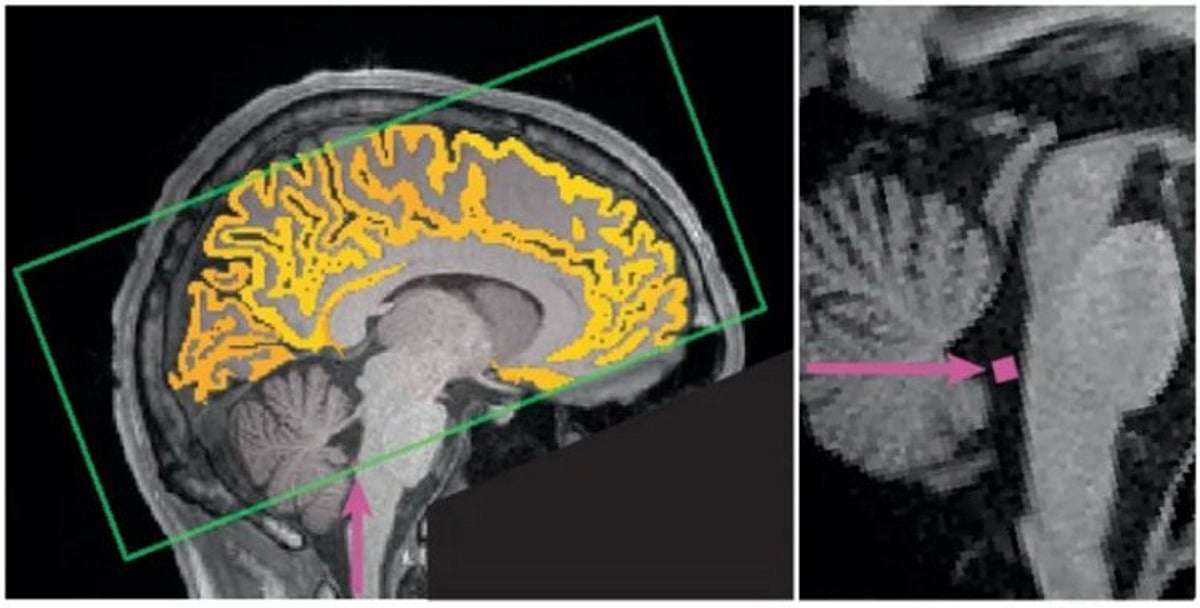

في توضيح علمي لافت، كشف البروفيسور أحمد بن سالم باهمام، أستاذ واستشاري الأمراض الصدرية وطب النوم بكلية الطب والمدينة الطبية في جامعة الملك سعود، عن نتائج دراسة حديثة توضّح تأثير الحرمان من النوم على الدماغ وصحة الإنسان العامة.